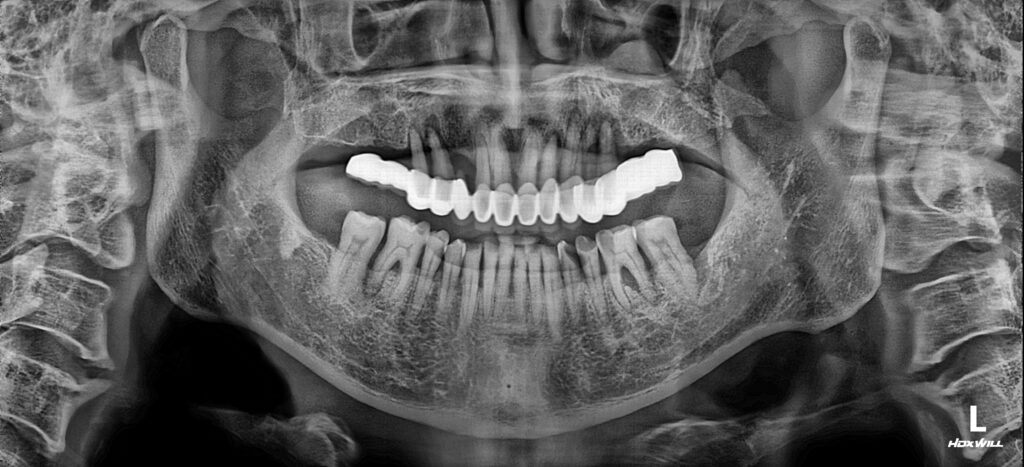

서울화이트S치과에 처음 내원하셨을 때 촬영한 파노라마 방사선 사진입니다. 상악은 모두 보철물을 하셨는데요. 대부분의 치조골이 흡수되어 모두 흔들리는 상태였습니다.

게다가 어금니는 인공 보철물로만 되어 있어 저작하실 때, 제대로 힘이 전달되지 않을 뿐만아니라 보철물 아래로 음식물이 많이 저류되고 관리하기 어려우셨으리라 생각됩니다.